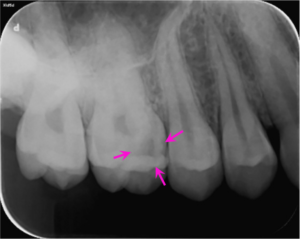

右上6番に大きな虫歯があり、虫歯の範囲が歯の中の神経に近接していました。通常の保険診療では歯の神経を抜く治療(歯の根の治療)になりますが、電気的な検査で神経の反応は正常であったので、虫歯治療と神経の保存療法(歯髄保存療法)を提案し、患者様の合意を頂いたので治療をすすめることになりました。

上のレントゲン写真では右上6番に虫歯で歯が溶けている部分があります(矢印部) 。